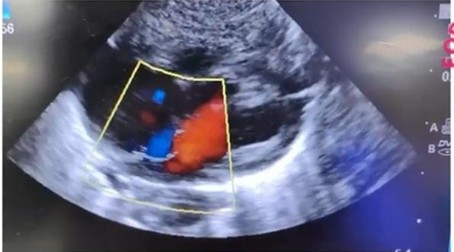

ECHO revealed critical pulmonary stenosis and a dysfunctional hypertrophied right ventricle with suprasystemic RV pressure. Prostaglandin E1 infusion was started and saturation improved.

Procedure Done: Balloon pulmonary valvuloplasty.

Balloon pulmonary valvuloplasty (BPV) was done at 46 hours of life. It’s a minimally invasive procedure to treat a narrowed pulmonary valve (stenosis) by inserting a catheter with a balloon guiding it to the valve and inflating the balloon to stretch open the valve leaflets improving blood flow from the heart to the lungs without open heart surgery.

Post-procedure, the PS gradient was reduced to 25 mmHg with good antegrade outflow. SpO2 improved to 96%, and PGE1 infusion was tapered and stopped. CPAP was gradually weaned off. Infant was extubated within 12 hr and was discharged in 4 days. On follow up at 4 weeks, he was growing well, had residual mild pulmonary stenosis and saturation was normal. Video clip added shows glimpse of the case and procedure.

Repeat ECHO

Repeat ECHO showed hypertrophied RV with improved RV function. IAS: 3 mm PFO with left-to-right shunt. Moderate TR, RVSP 35 + RAP. Pulmonary valve thick, bicuspid with good antegrade flow. RVOT gradient due to residual valvular PS – 25 mmHg, mild PR. S/p BPV for critical pulmonary stenosis – mild RVOT with good biventricular function.